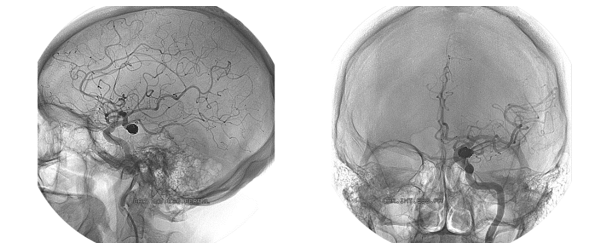

Pasirinkus endovaskulinę embolizaciją, atliekama minimaliai invazyvi operacija, kurios metu per šlaunies arteriją kirkšnies srityje įvedami specialūs kateteriai, kurie keliauja per aortą ir kaklo arterijas iki smegenyse esančios aneurizmos. Tada per juos į aneurizmą yra įvedama speciali platininė embolizacinė spiralė, kuri užpildo aneurizmą ir taip „uždaro“ kraujo pritekėjimą į aneurizmą. Esant plataus kaklelio, didelės, neįprastos formos, sudėtingoje vietoje esančioms aneurizmoms, naudojamas stentas – srovės nukreipėjas (angl. flow diverter).